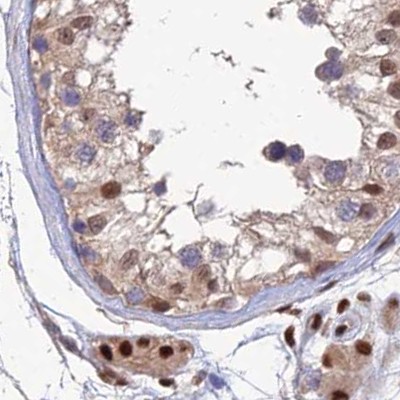

Immunohistochemical staining of human cerebral cortex, lymph node, pancreas and testis using Anti-DNPEP antibody HPA044860 (A) shows similar protein distribution across tissues to independent antibody HPA036398 (B).